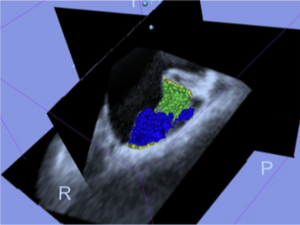

- 3.9 Automatic Classification of Prostate Cancer Gleason Scores from Multiparametric Magnetic Resonance Images